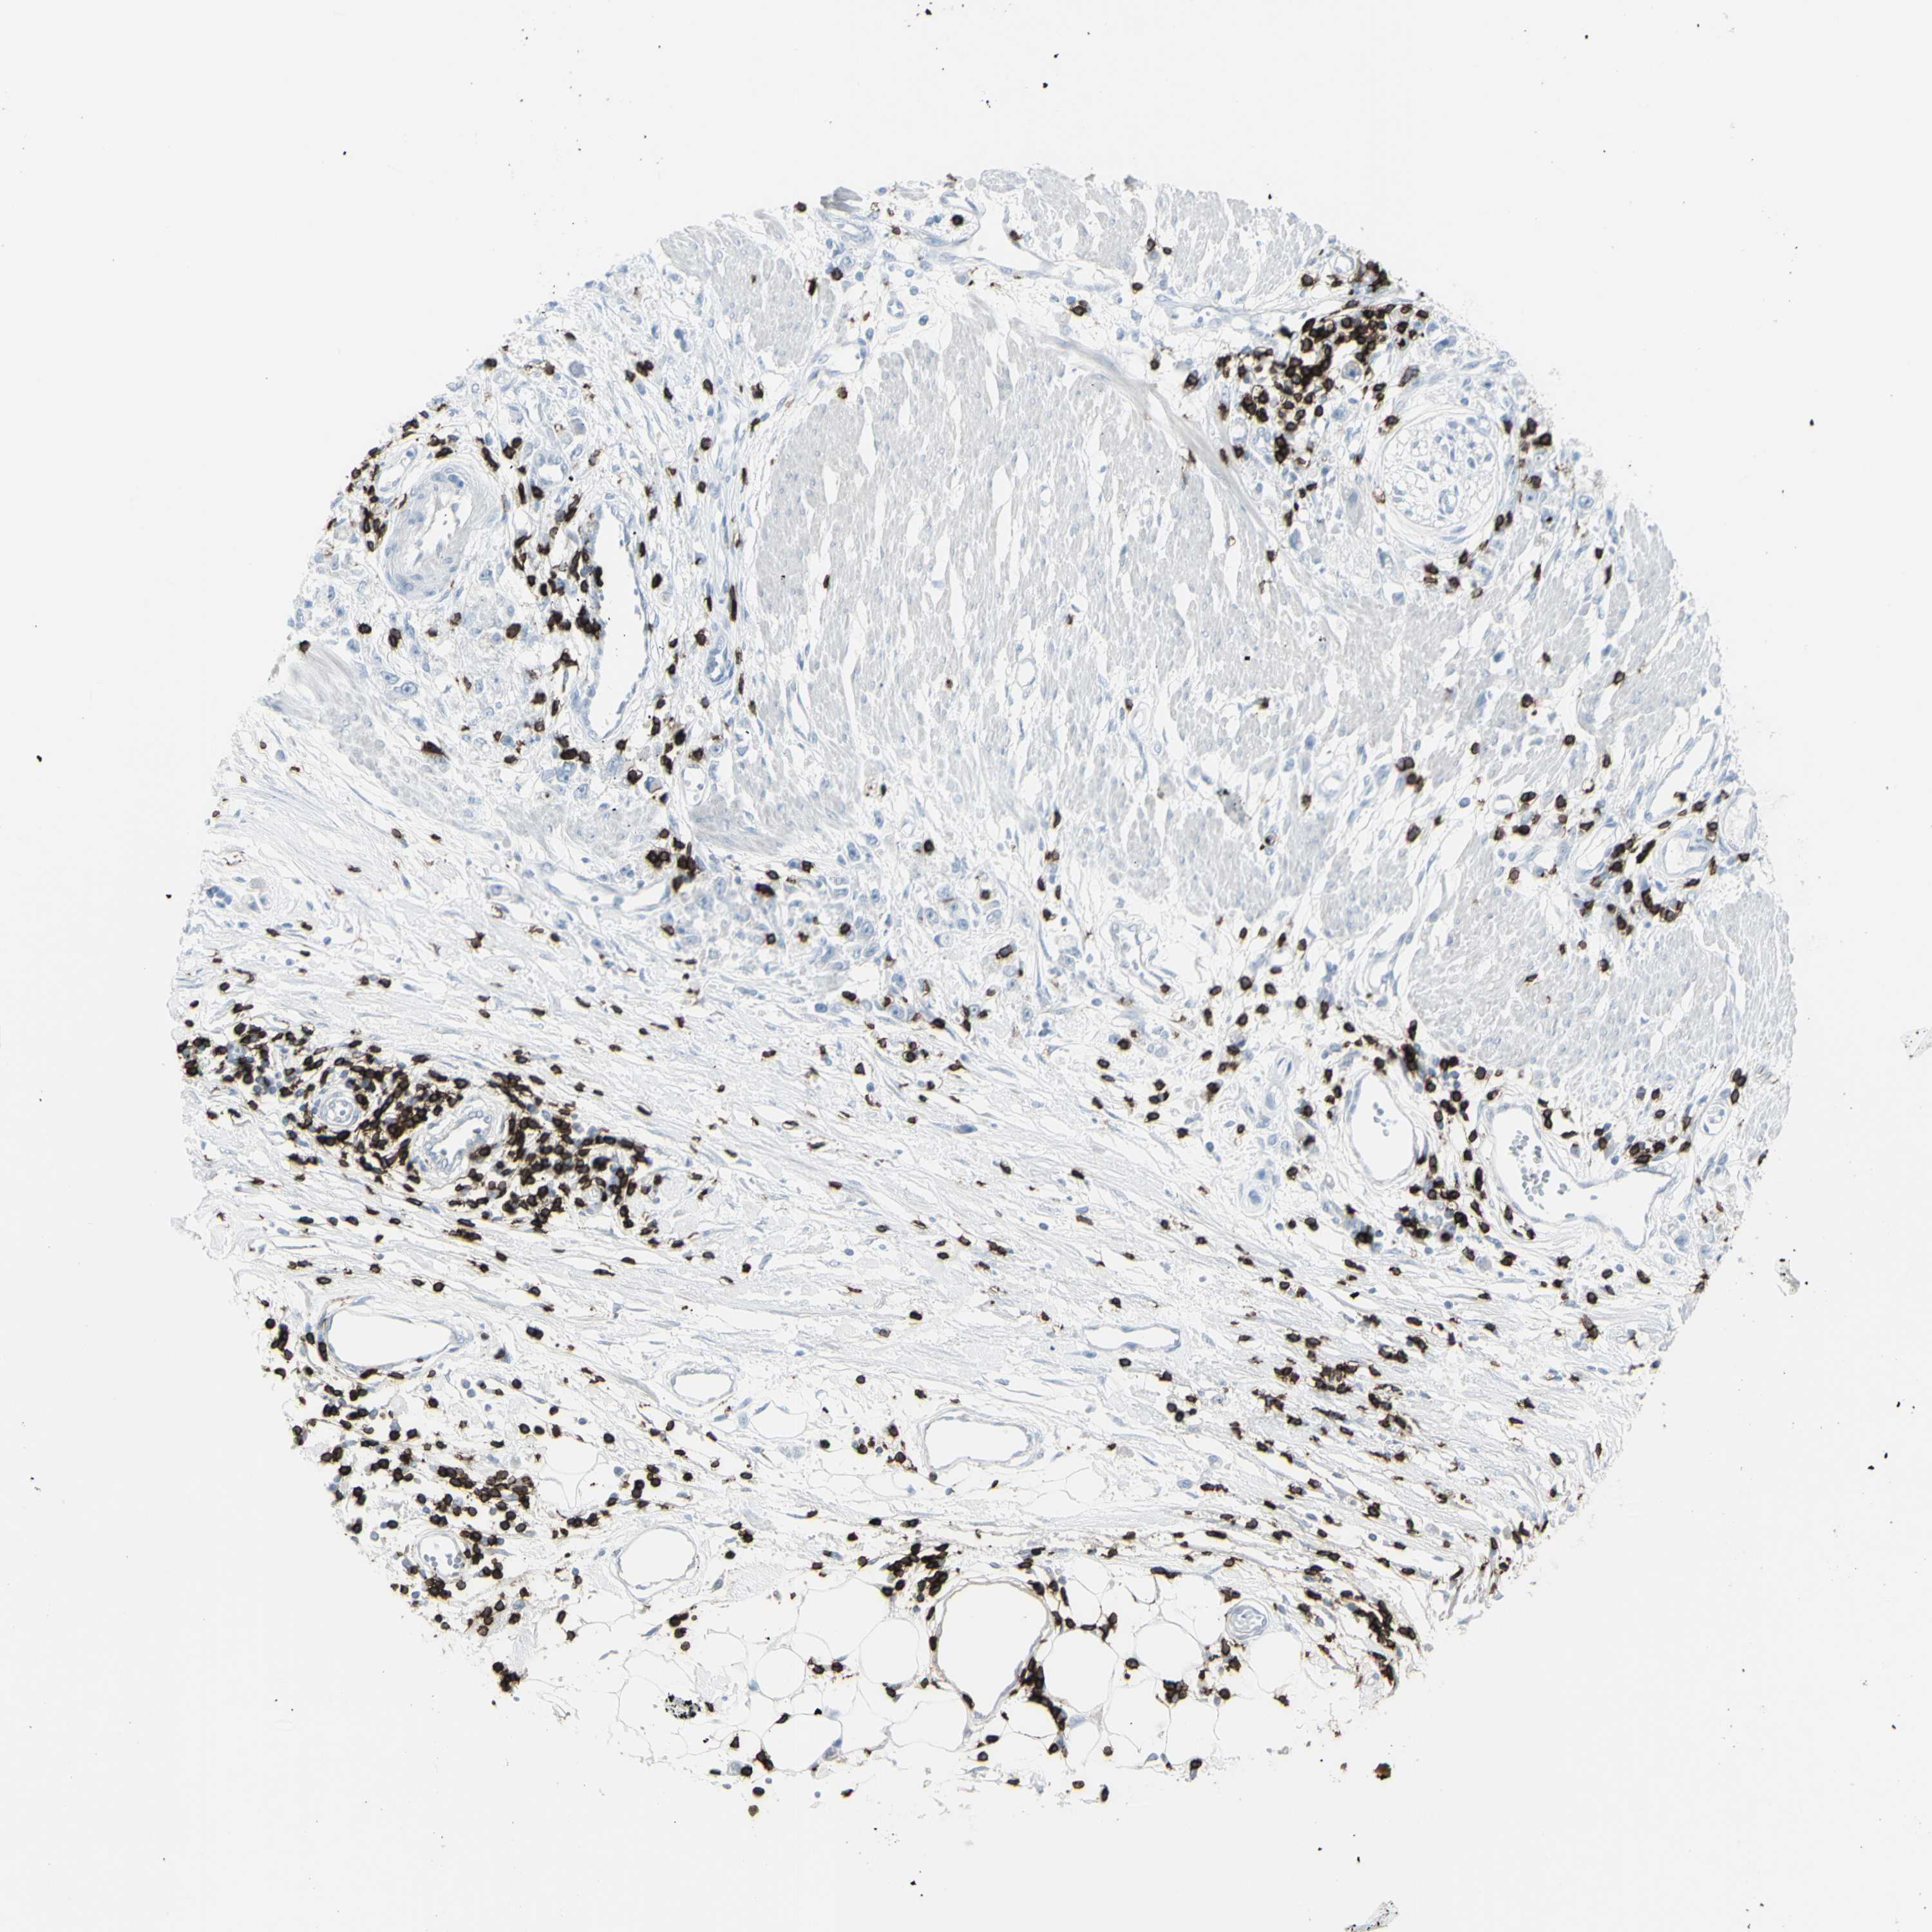

STOMACH CANCER - Protein expressioni

A mouse-over function shows sample information and annotation data. Click on an image to view it in a full screen mode. Samples can be filtered based on level of antibody staining by selecting one or several of the following categories: high, medium, low and not detected. The assay and annotation is described here.

Note that samples used for immunohistochemistry by the Human Protein Atlas do not correspond to samples in the TCGA dataset.

Antibody stainingi

Antibody staining in the annotated cell types in the current human tissue is reported as not detected, low, medium, or high, based on conventional immunohistochemistry profiling in selected tissues. This score is based on the combination of the staining intensity and fraction of stained cells.

Each image is clickable and will lead to virtual microscopy that enables deeper exploration of all samples and also displays staining intensity scores, fraction scores and subcellular localization as well as patient and tissue information for each sample.

Antibody HPA008750

Antibody CAB004651

Staining

High

Medium

Low

Not detected

Intensity

Strong

Moderate

Weak

Negative

Quantity

>75%

75%-25%

<25%

None

Location

Nuclear

Cytoplasmic/membranous

Cytoplasmic/membranous,nuclear

Adenocarcinoma, NOS

Adenocarcinoma, High grade